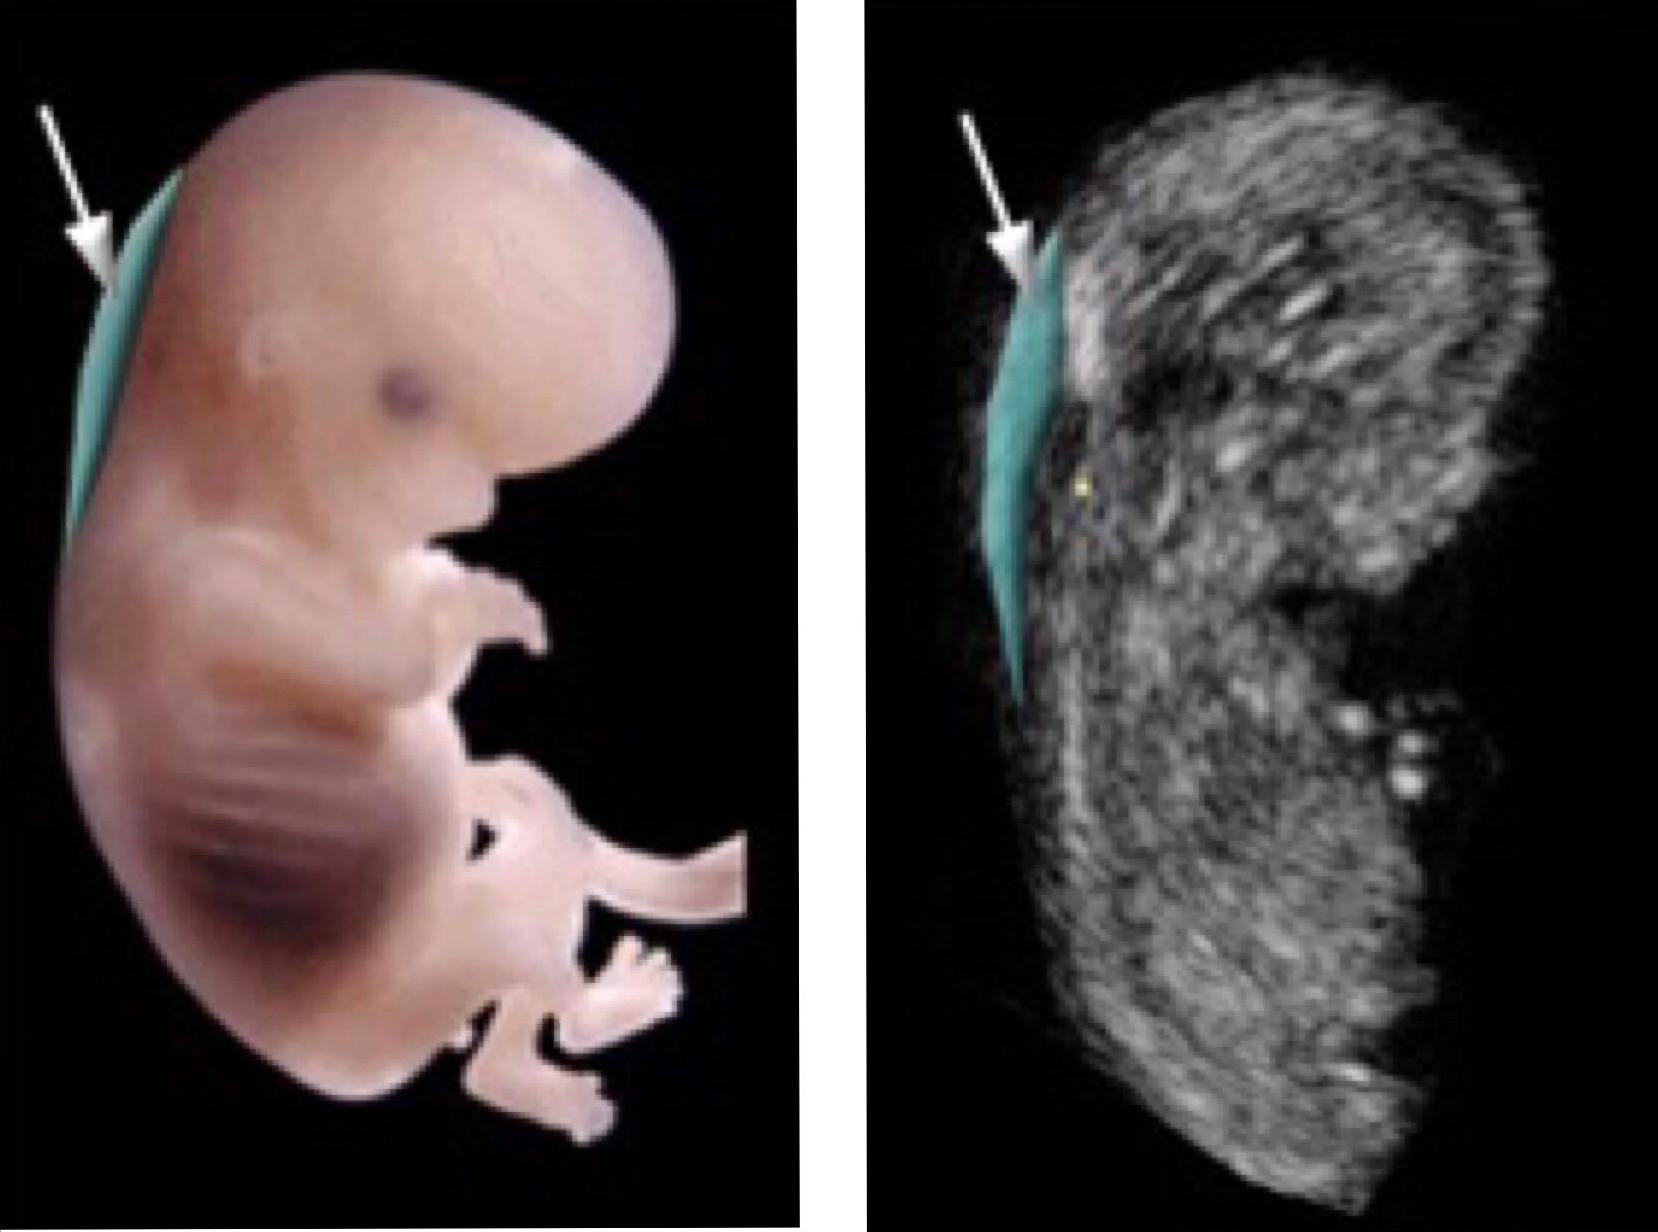

NT检查,也就是“胎儿颈项部透明层”检查,它是孕期的第一次排畸检查,非常重要,而且,一旦错过时间就无法做了。

NT检查的主要作用就是排查胎儿染色体的异常和畸形,它能够使大多数的胎儿畸形更早地被发现,方便及时进行诊断和干预。

NT检查最佳的检查时间是在孕11周0天~13周6天之间,太早的话可能会看不清,太晚了结果就不准确了。需要注意的是,这项检查很多医院都需要提前预约,所以,准妈妈们要提前预约,以免错过检查时间。